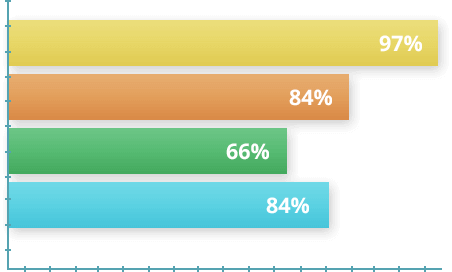

НЕЗАЛЕЖНІ ДОСЛІДЖЕННЯ

У 2020 році було проведено дослідження за участю 1700 добровольців з різним ступенем занедбаності захворювання суглобів. Згідно з умовами, випробувані протягом перших 30 днів використовували Artronil® двічі на день. Далі йшов 30-денний відпочинок і за необхідності повторення курсу. Після закінчення експерименту на на підставі отриманих даних було складено статистику.

- 97% учасників відчули миттєве полегшення болю

- 84% піддослідних перемогли хворобу за один курс лікування

- 66% повернулися до активного життя через тиждень після закінчення курсу

- 81% відзначили загальне поліпшення самопочуття та приплив сил